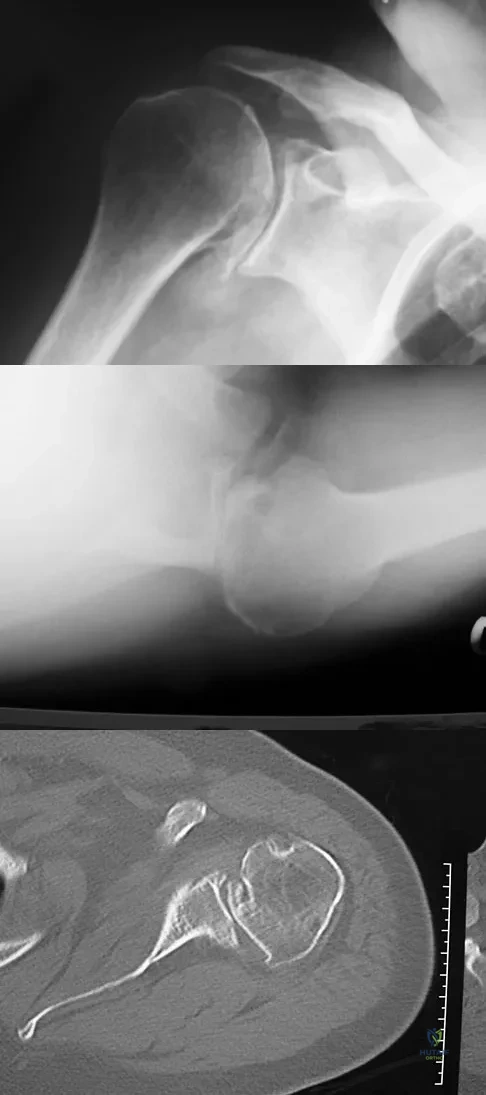

A 68-year-old man had a 3-year history of shoulder pain that failed to respond to nonsurgical management. Examination reveals forward elevation to 120 degrees and external rotation to 30 degrees. True AP and axillary radiographs and an axial CT scan are shown in Figures 1a through 1c. What management option would lead to the best long-term results?

Figure 33 shows the CT scan of a 40-year-old man who injured his left shoulder while skiing. What structure is attached to the bony fragment?